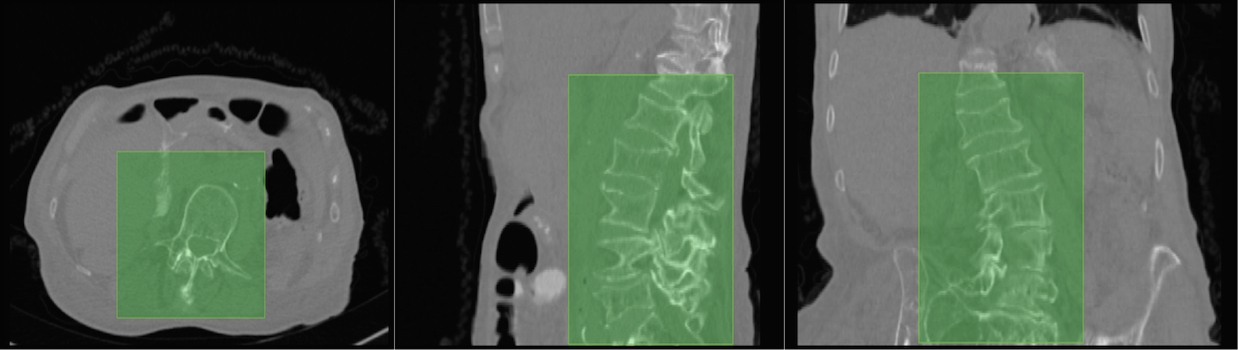

2.1.2 Estimation of the lumbar bounding box

Each pass through the regressor using a feature corresponding to a certain voxel predicts the locations of the bounding planes with respect to that voxel. In order to speed-up the feature generation procedure without loss of useful information, only the significant voxels are considered for feature extraction. For this purpose, the voxels from the response of a Canny’s edge detector are used for feature extraction. Thus, every significant voxel votes for a prospective bounding box of which the most representative bounding box is chosen. Figure 2 shows a few examples of the localised lumbar regions.

2.2.3 ROI Augmentation

Another key concept in our segmentation routine is the ROI augmentation step. However, the localisations are not uniform as shown in figure 2. There could either be non-lumbar vertebrae showing up in the sagittal slices (usually T11 and T12 in our experiments), or part of the lumbar region could be missing (usually L1 in our experiments). The high correlation in the appearance of the vertebrae makes this problem detrimental. Therefore, in addition to augmenting the sagittal slices using elastic and rigid transformations, we also augment based on varying bounding boxes sizes. Let be the dimension of the lumbar bounding box obtained from the localisation stage. We augment the sagittal slices from bounding box by randomly choosing a so that the sagittal slice dimensions vary between and . This makes the segmentation network robust to improper lumbar localisations.

3.0.2 Lumbar localisation

Inspired from [6], a five-layered neural network is cast as a regressor to map the features () to the offsets of the bounding planes (). The input layer has (=500) neurons, followed by four hidden layers with 350, 250, 150, and 50 neurons respectively. The output layer has six neurons corresponding to the offsets of the six bounding planes. All the neurons are ReLUs. The network was implemented in the Caffe [8] framework. A squared-error loss was optimised using stochastic gradient descent. The available data was augmented with rigid and elastic transformations. The network was trained for 1000 epochs over a few hours with a learning rate of 1e-3 and a momentum of 0.9. The most representative bounding box is chosen using kernel density estimation, aided by Botev bandwidth [9] selection.

To measure the performance of localisation, a measure of sensitivity (or true positive rate) was used, as defined:

where is the of set voxels in the ground truth segmentation, and is the set of voxels within the bounding box. We use the ground truth segmentation for Rater-1 for this purpose. The sensitivity measures on the test set are shown in table 1, with a few cases shown visually in figure 2. We obtain a near perfect localisation of 1.0 in all cases except one (Case025). In order to completely cover the lumbar region, a tolerance of 15 voxels is added to the bounding boxes on all sides before considering the localisation for for the next stage.

The curious case of Case025: Case025 of the test set is peculiar due to the presence of the entire sacrum (S1, S2, and S3) within the FOV. It is the only such case in the train and the test data. The network thus furnishes an imperfect localisation from L2 to S1. Such a behaviour can be easily rectified with additional representative training data.